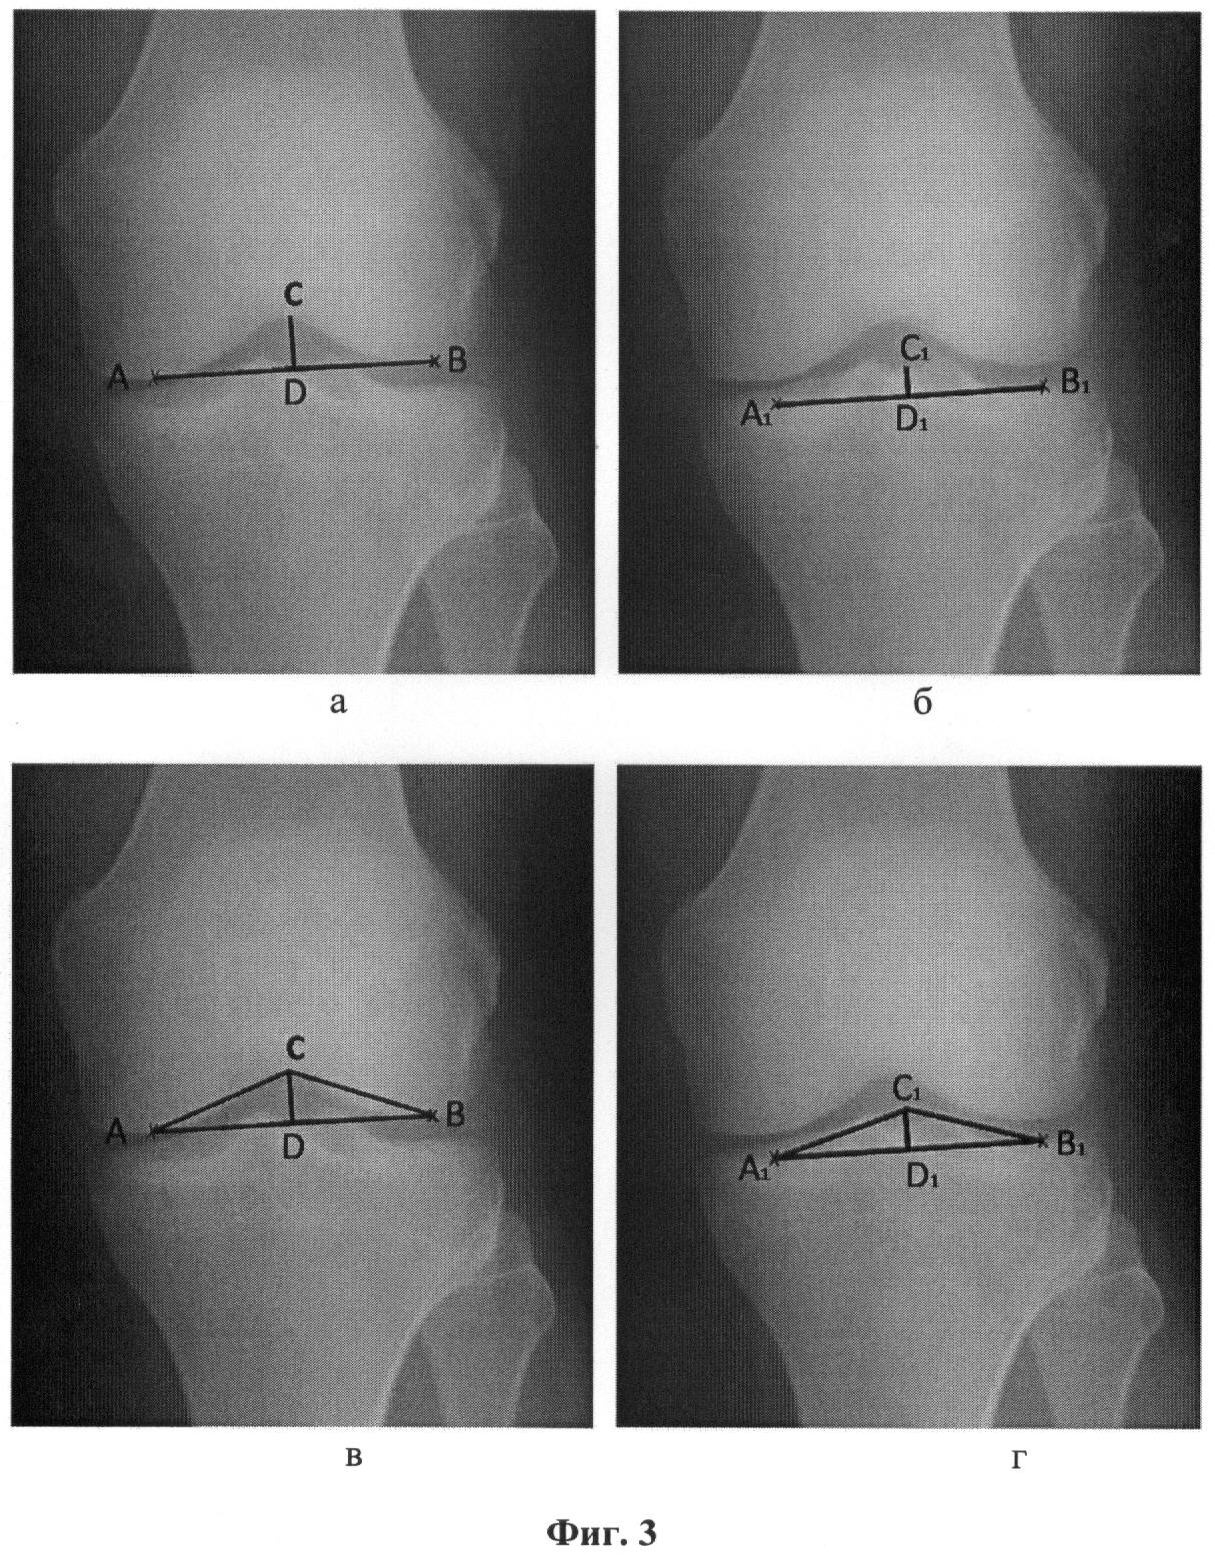

Фиг.4 – рентгенограмма правого коленного сустава пациента С., 56 лет, а – точки отсчета и линии для определения индексов межмыщелковой ямки; б – точки отсчета и линии для определения индексов межмыщелкового возвышения; в – точки отсчета и треугольник для определения углов мыщелков бедренной кости; г – точки отсчета и треугольник для определения углов мыщелков большеберцовой кости.

На рентгенограмме коленного сустава в переднезадней проекции (фиг.4) ИМЯ составляет 7,0, и ИМВ – 8,1, что свидетельствует о наличии признаков дисплазии мыщелков бедренной и большеберцовой костей. Повышенные функциональные нагрузки приводят к связочно-капсульной нестабильности сустава и возникновению болевого синдрома на фоне диспластической болезни.

Констатируется дисплазия сустава и по данным величин углов , 1 – 16° внутреннего и наружного мыщелка бедренной и величин углов , 1 – 13° внутреннего и наружного мыщелка большеберцовой костей.

По установленному диагнозу пациенту было рекомендовано исключение высоких нагрузок, проведение физиотерапевтического лечения и диспансерное наблюдение у ортопеда.